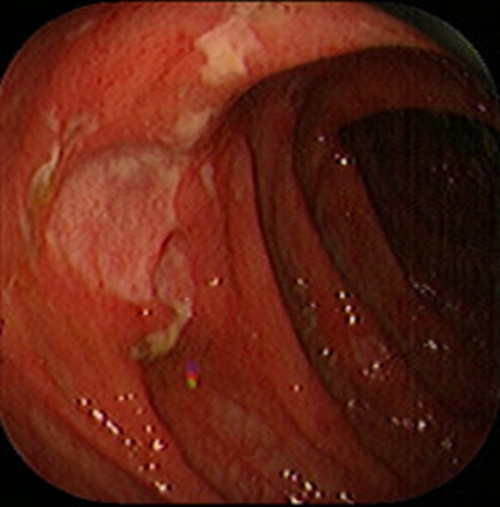

急性胃炎圖片

急性胃炎陽性表現

急性胃炎陽性的表現

急性胃炎

急性胃炎陽性表現的

急性胃炎的陽性的表現